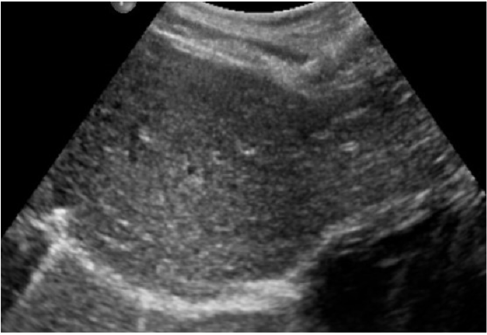

Due to the hemodynamic stability, the patient was admitted into the pediatric intensive care unit (PICU) for the first 72 hours. Clinical examination and laboratory tests were performed daily without anemizing secondary to liver bleeding (hemoglobin level of 13.8 g/dL on day 7). Ultrasound controls were performed each 48 hours. Three days after admission, the patient had a good clinical status, enteral nutrition was restarted, and the abdominal pain had also disappeared. The laboratory test showed total bilirubin (B) level of 7 μg/L, gamma-glutamyl transferase (GGT) levels of 48 U/L, glutamic-pyruvic transaminase (GPT) levels of 121 U/L and glutamic-oxaloacetic transaminase (GOT) levels of 41 U/L. The patient was discharged on day 7 with a good clinical status. Two weeks later, a clinical control in the outpatient department revealed no clinical or laboratory abnormalities and an abdominal ultrasound revealed a practically remission of the previous abnormal findings. During outpatient follow-up, the liver injury was resolved after 1 month of ultrasound controls (Figure 2). No complications were diagnosed after 3 years of follow up and the patient remains asymptomatic.

Clinical examination and laboratory tests are mandatory. The process of analysis and monitoring of arterial blood gasses and blood tests are an essential part of diagnosing and managing of the patients specially during the first 48 hours. The standard radiological control recommendation by the American Pediatric Surgical Association (APSA) is summarized in the guidelines for the use of resources in patients with blunt abdominal trauma (BAT) with SOI (Table 2) [4,5]. However, in our center we apply this protocol partially adapted to the characteristics of our hospital setting, performing ultrasound controls during the hospital admission of SOI every 24-48 hours in grades II-V.

Ambulatory controls (one control at least) are carried out without performing radiological studies by routine, except for clinical suspicion or persistence of radiological lesions in previous controls, indicating ultrasound control as radiological test of choice until resolution of them monthly.